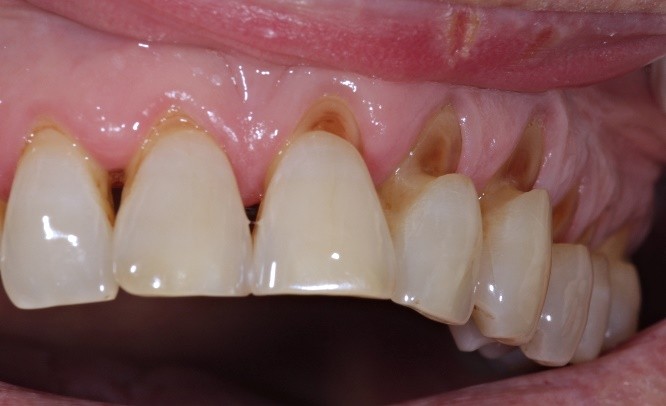

If your teeth appear shorter, flatter, or have worn-down occlusal cusps, you may already be experiencing occlusal trauma. Other warning signs include chipping or fracturing of teeth and restorative work such as fillings, veneers, or crowns. These are not merely cosmetic issues—they indicate that applied forces generated between the upper and lower dentition exceed the tolerance of tooth tissues. When these excessive forces surpass the enamel’s ability to withstand pressure, microfractures, chipping, and accelerated wear occur.

- Tooth sensitivity: As enamel wears down, the underlying dentin becomes exposed, leading to heightened sensitivity to temperature and pressure.

- Damage to dental restorations: Existing fillings, crowns, or veneers can be damaged or worn away by excessive occlusal forces.

- Untreated occlusal wear progression: It creates a snowball effect—deterioration progresses more rapidly over time, leading to increasingly harmful consequences at a much faster rate. As occlusal wear progresses, the deterioration becomes continuous and increasingly difficult to control. In the more advanced stages, the process accelerates, leading to faster breakdown of tooth structure and greater functional instability.